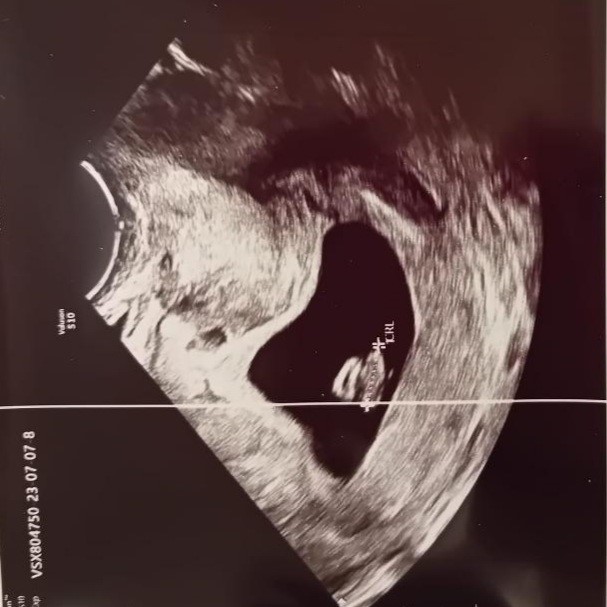

After two weeks of the embryo transfer, we received a positive pregnancy test and after 4 weeks of the embryo transfer, a vaginal ultrasound detected a fetus in the uterus, with a positive heartbeat (Figure 2).

Figure 1. HSG- hysterosalpingography. Figure2. Pregnancy detection with US.

Ultrasound examinations monitoring of fetal growth and development and cervical length were performed every 2-3 weeks. Detailed ultrasound screenings of the fetus were performed in the first (Figure 3) and second trimesters (Figure 4) of pregnancy, infectious screenings by taking microbiological smears and serological analyzes at the end of the first trimester in the 12th week of gestation, biochemical investigations and genetic screening due to the mother’s age – 39 years were performed, and were with normal finding.

Figure 3. US screening in 1st trimester. Figure 4. US screening in 2nd trimester.